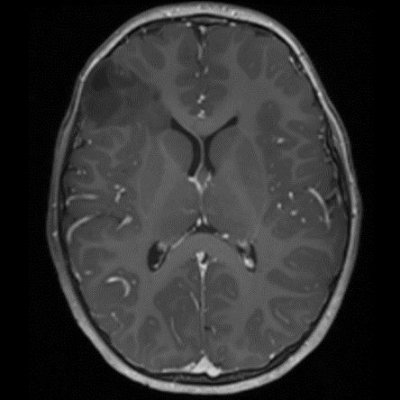

DNET:Özellikle erkek çocuk ve nöbet öyküsüyle gelen hasta kortikal yerleşim ve t1 ağırlıklı serilerde hipointens t2a ve flair serilerde ise hiperintens görülmesi bu tanıma uymaktadır. Hastaların 5’te birinde frontal lobda da tutulum olabilir. Lezyon çevresinde ödem ya da içerisinde kalsifik odak izlenmemiştir:

DNET:Özellikle erkek çocuk ve nöbet öyküsüyle gelen hasta kortikal yerleşim ve t1 ağırlıklı serilerde hipointens t2a ve flair serilerde ise hiperintens görülmesi bu tanıma uymaktadır. Hastaların 5’te birinde frontal lobda da tutulum olabilir. Lezyon çevresinde ödem ya da içerisinde kalsifik odak izlenmemiştir.